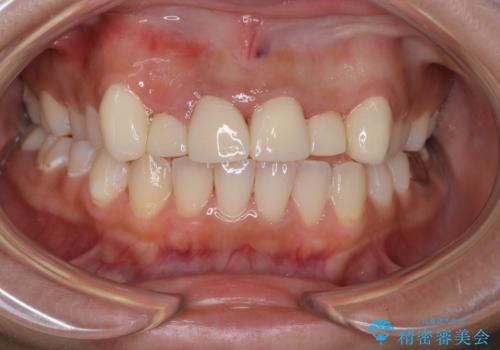

- セラミック矯正希望で来院された患者さんです。

歯周組織の状態が悪く、この状態ではきれいにかぶせものを入れることができないため、仮歯にかえてある程度見た目を改善した上で、歯周基本治療を進めることに。

歯肉の状態が改善できたら、セラミックに変えていく治療計画を立てました。